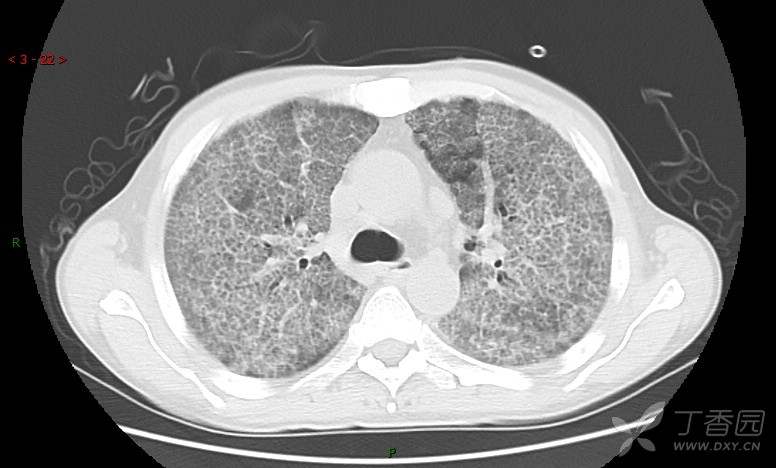

地图+铺路石征=PAP?那升高的CEA怎么说(病例3连发,附其他2例链接)

患者男,42岁,咳嗽半年余,加重伴憋喘2月余。

患者半年余前无明显诱因出现间断咳嗽,干咳为主,偶咳少量黄白痰,剧烈咳嗽或运动后可出现轻度憋喘,无高热、脓臭痰,无胸痛、咯血及晕厥,无低热乏力及盗汗,无心前区压榨感及夜间阵发性呼吸困难,初未在意,未予正规诊治。2月余前患者自觉上述症状较前加重,咳嗽、憋喘明显,黄白色粘痰略有增多,伴有发热,热前伴有畏寒、寒战,体温最高达38.9℃,先后就诊多家医院,入住重症监护室,未行气管插管,考虑“重症肺炎”,给予“美罗培南、复方磺胺甲噁唑”等药物抗感染,“卡泊芬净”抗真菌,并给予“甲泼尼龙”等药物治疗35天,经治疗后症状好转于2018-04-02出院。患者自出院后仅应用中药治疗(具体不详),并给予家庭氧疗,平素仍有间断咳嗽,咳少量黄白色粘痰,活动后憋喘明显,活动耐量差,以卧床为主。

肺内弥漫性网状结节影,PET-CT却无阳性病灶,这是?(附其他2例链接)